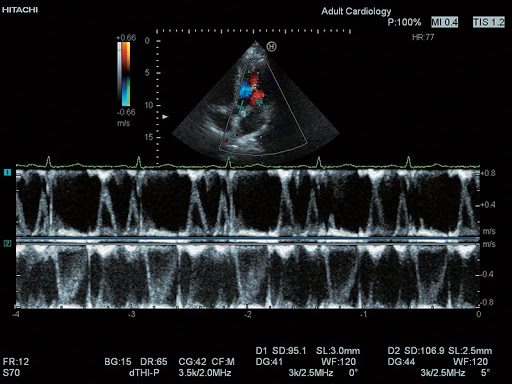

Dual Gate Doppler (Двойной Допплер)

- TDI – режим тканевого допплера

EUP-S70 – Секторный фазированный датчик для проведения эхокардиографических исследований взрослых.

Также подходит для транскраниальной допплерографии.

Диапазон частот: 1 - 5 МГц

Угол сканирования: 90°